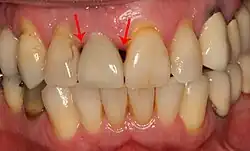

Fixture show

Recession of the gingiva leads to exposure of the metal abutment under a dental crown.

Black triangles

Black triangles caused by bone loss between implants and natural teeth